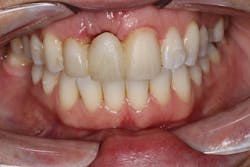

These alveolar bone changes often compromise implant placement due to thin bone volume (figures 2a–2d).

Reduction in quantity and quality of bone can also compromise functional and esthetic outcomes of both implants and fixed bridge restorations (figures 3 and 3a).